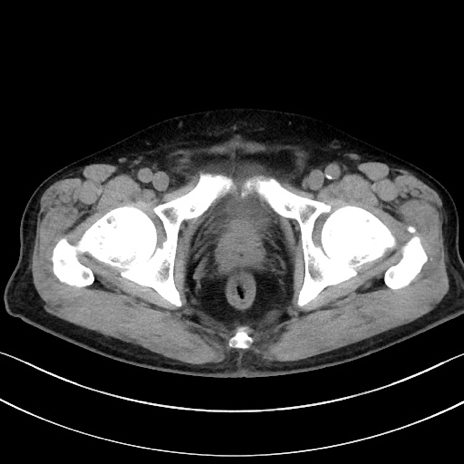

症例15(横断像)

【症例】70歳代男性

【主訴】腹痛

【現病歴】今朝から腹痛あり。全体的に痛い。特に左上の方。排ガスが今日はない。冷や汗が出る。

【既往歴】直腸癌術後

【身体所見】左側腹部〜上腹部に圧痛あり。腹膜刺激症状明らかなではない。軽度反跳痛。左下腹部に術後瘢痕あり。

【データ】WBC 7700、CRP 0.02